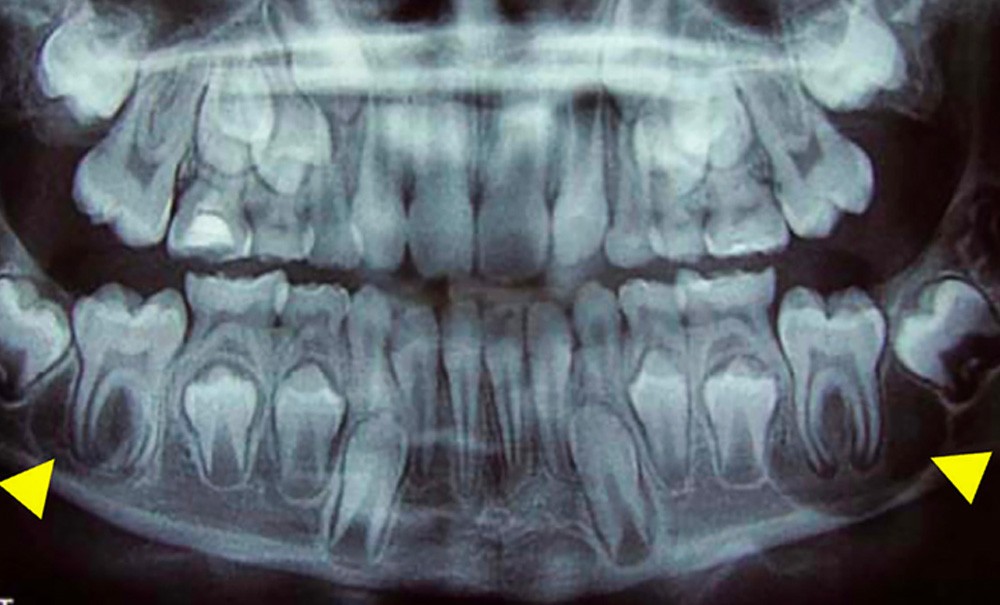

Le kyste de la furcation vestibulaire, également retrouvé sous le terme de kyste mandibulaire vestibulaire surinfecté, est une lésion kystique rare et encore largement méconnue, pouvant être une source d’erreurs diagnostiques et thérapeutiques. Classés par l’Organisation Mondiale de la Santé (OMS) dans les kystes inflammatoires paradentaires (i.e collatéral), cette lésion kystique est souvent retrouvée chez les patients jeunes car elle touche préférentiellement les molaires mandibulaires au moment de leur éruption (fig. 1). Son étiologie est incertaine. Lors de l’éruption d’une molaire mandibulaire, une inflammation surviendrait et déclencherait une prolifération épithéliale dans l’espace desmodontal. Ce kyste peut mimer une pathologie parodontale ou endodontique classique alors même que la dent concernée est vivante.